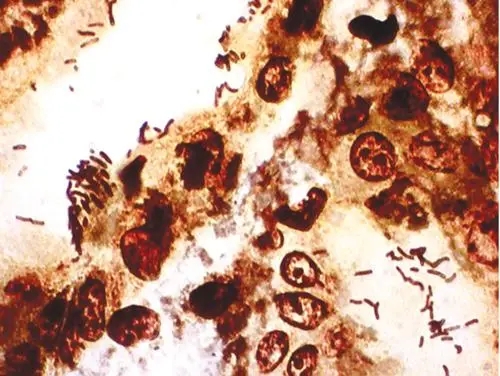

细胞自身的“健康状况”是生长的基础。传代次数过多(超过30代)会导致细胞出现复制性老化,表现为端粒缩短、衰老相关β-半乳糖苷酶活性升高,增殖能力自然下降。此外,隐性污染是最容易被忽视的问题——支原体污染率高达30%,它会掠夺细胞营养、分泌毒性物质,导致细胞生长缓慢但镜下无明显异常(如细菌污染的浑浊现象)。